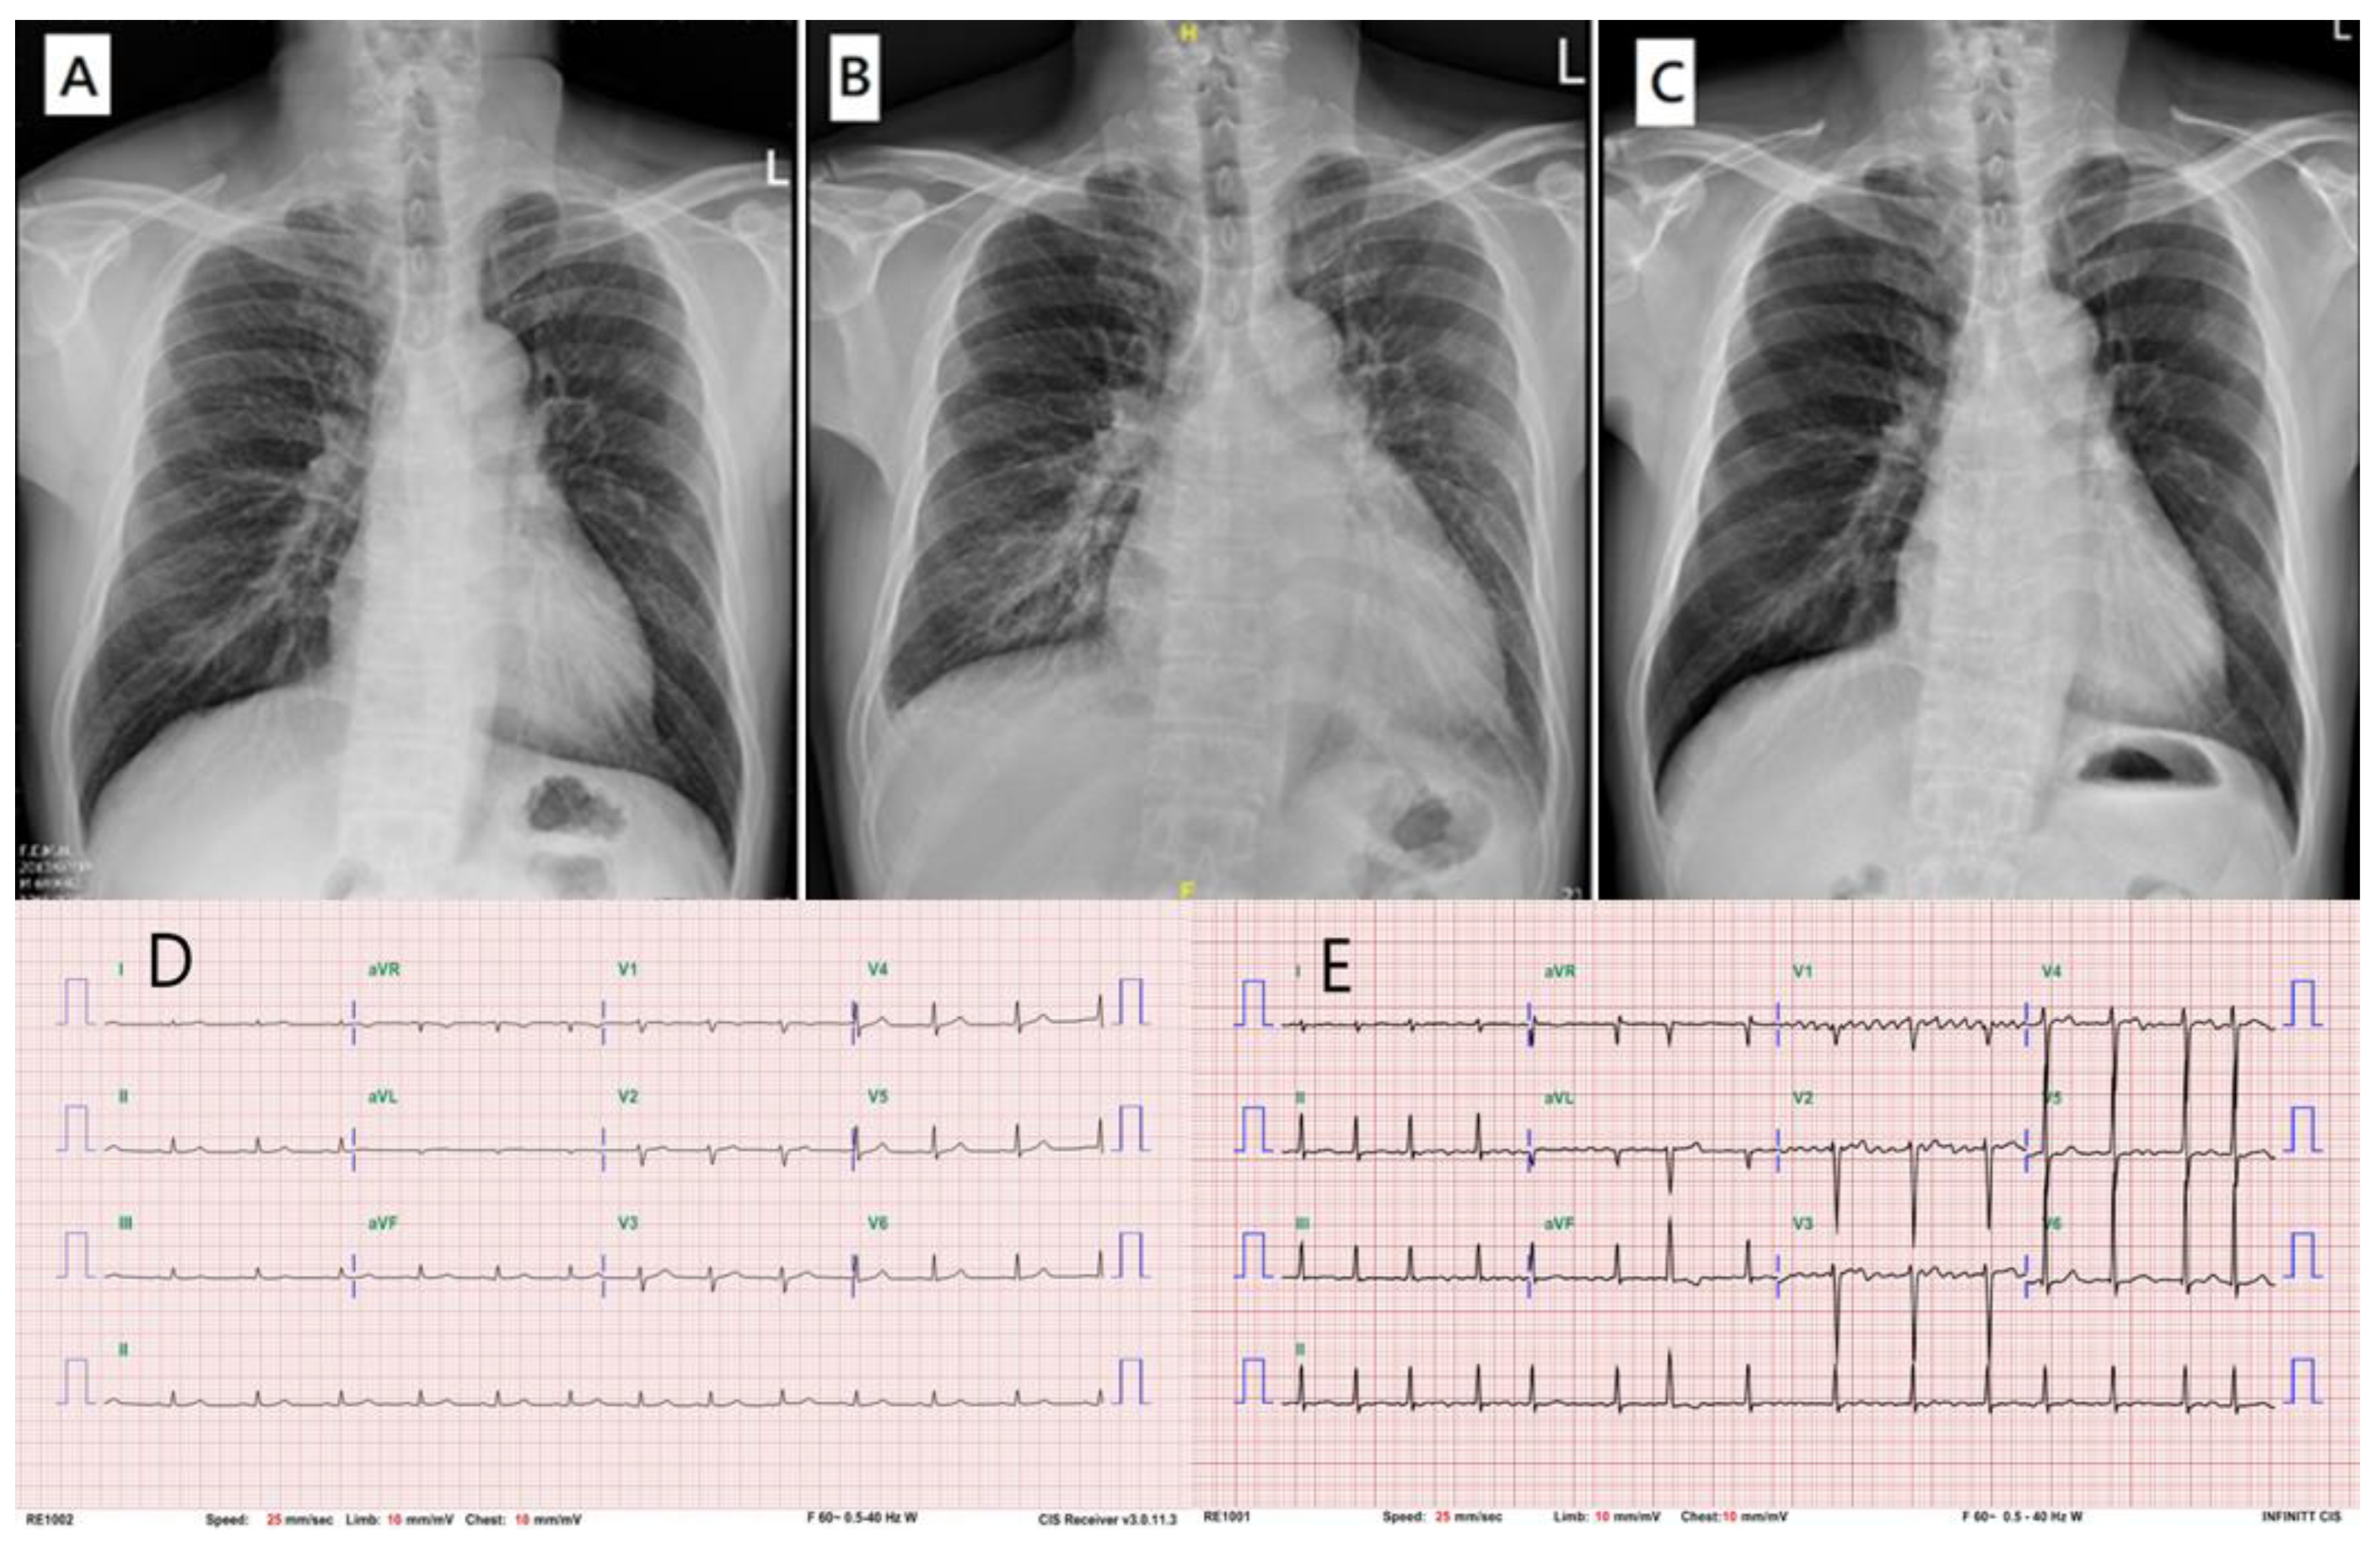

2. Case Report

2.3. Proband

2.4. Affected Kindred